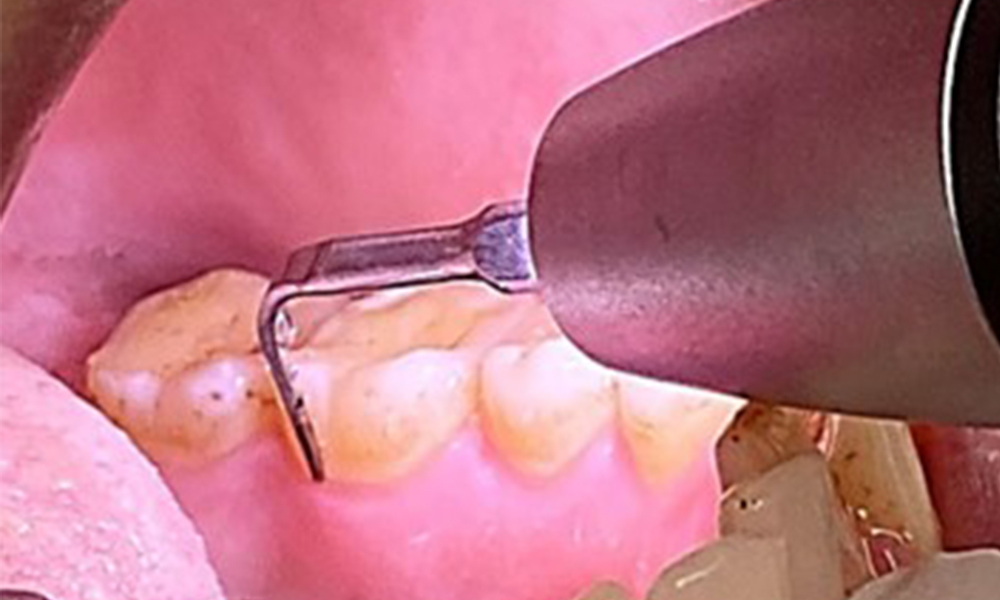

It is also necessary to check that the interdental brushes – used by this patient on a daily basis – are the correct size and encourage consistent use (Fig. 9). Good intraoral hygiene minimizes the risk of periodontitis from smoking.

Use of the interdental brushes in the area near 44/45

Fig. 9: Use of the interdental brushes in the area near 44/45, © Dr R. Krapf